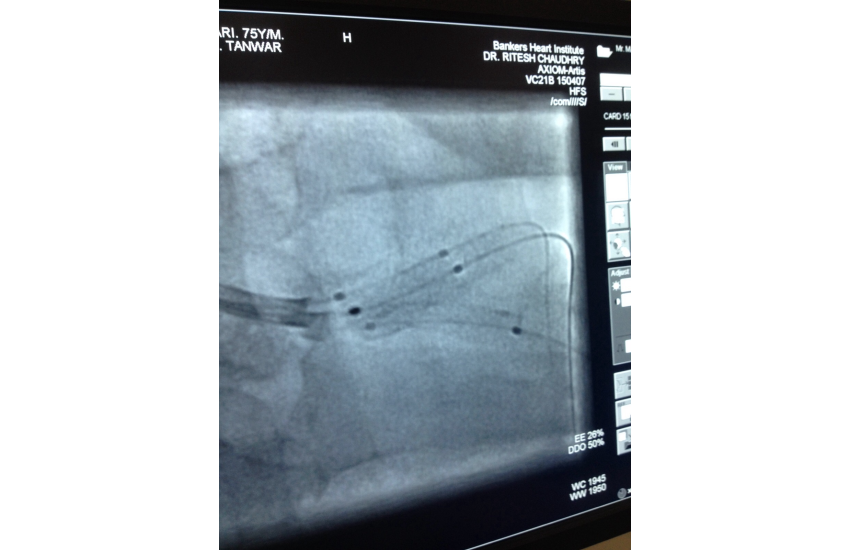

75 years old male presented with unstable angina undergone CAG which is shown LMCA bifurcation lesion first option given for CABG surgery but Pt. is not willing for that so after discussing all the risk of LMCA bifurcation kissing steanting Than patient and relatives ready for that and with all life support system successfully done by Dr N T sir. After steanting patient is doing well.